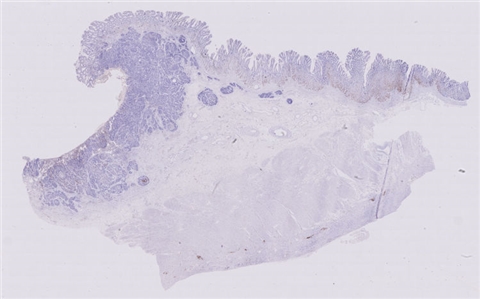

性别:       年龄:41

患者详情: 患者诉1天前无明显诱因出现脐周腹痛,持续性钝痛,不向远处部位放射,进食后感恶心,无呕吐,无发热、腹泻等不适,后腹痛逐渐转移至右下腹,遂来我院诊治,门诊拟“急性阑尾炎”收住入院,临床拟急性阑尾炎行手术切除。

大体所见: 阑尾一条,长4.0厘米,管径0.7-0.9厘米,浆膜面灰白色、附有脓苔。

免疫组化: 肿瘤细胞:CDX-2(+)、CEA(+)、CK(+)、ECD(+); P53(+),SATB-2(+),CD56(少量+),CgA(-),syn(+)

医院: 赣州市人民医院